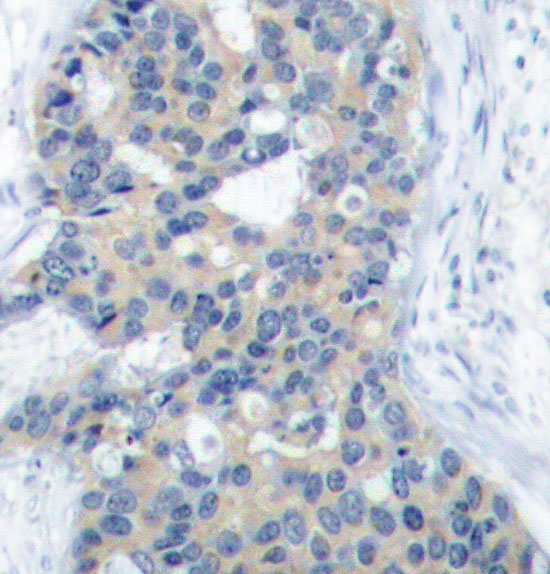

• AP0221: image 2

Immunohistochemical analysis of paraffin-embedded human breast carcinoma tissue using Phospho-STMN1-S38 antibody.